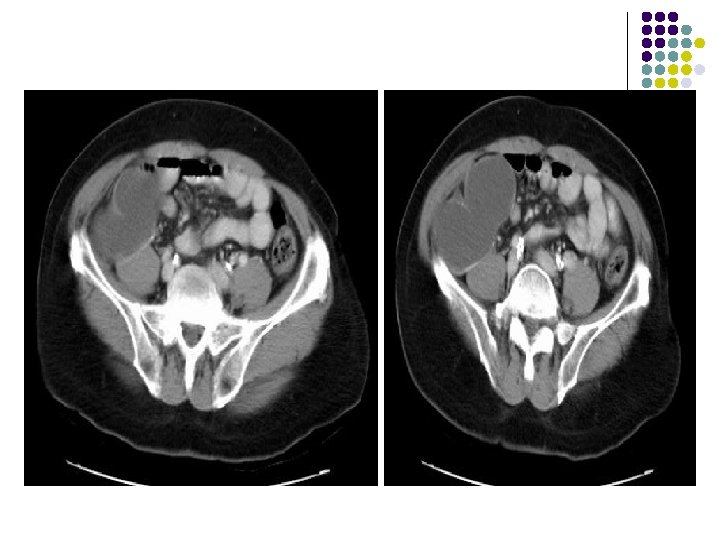

CT: l Tumor has soft-tissue attenuation (May contain foci of low attenuation (hemorrhage/necrosis) l Well-defined margins WITHOUT rim of sclerosis MRI l Heterogeneous signal intensity with low to intermediate intensity on T 1 WI & T 2 WI due to collagen and hemosiderin content.

Axial ct of proximal leg-Soft tissue attenuation with well defined margins and foci of low attenuation within due to h’age or necrosis. Coronal CT scan of a giant cell tumor of the distal ulna show soft tissue attenating lesion.

T 2 -weighted coronal MRIs of the wrist show a giant cell tumor located in a subarticular position in the distal radius. The lesion is heterogeneous and hyperintense.